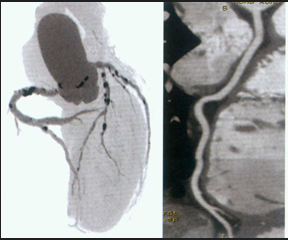

冠状动脉CT造影及钙化评分。盖斯顿教授建议,如果你年过半百,此项检查很有必要;有心脏病高危因素或者有家族史的人也应检查冠脉钙化情况;因X线有辐射,怀孕女性不能做。钙化评分在400以上,说明未来10年内心脏病风险增高;评分超过1000,意味着1年内如果不治疗,心脏病风险增加25%。评分超过200,可以通过调整生活方式、吃降脂药等减少血管内斑块。